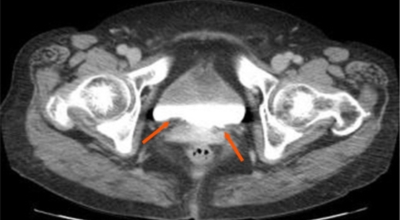

2. 방광암 초기증상 - 부종

통증이나 요관폐색으로 인해 배뇨가 잘 되지 않을 경우 방광암 초기증상으로 부종이 나타날 수 있어요. 하지에 부종이 생기거나, 암이 어느정도 진행된 경우 골반 주변에서 덩어리가 만져지기도 합니다.